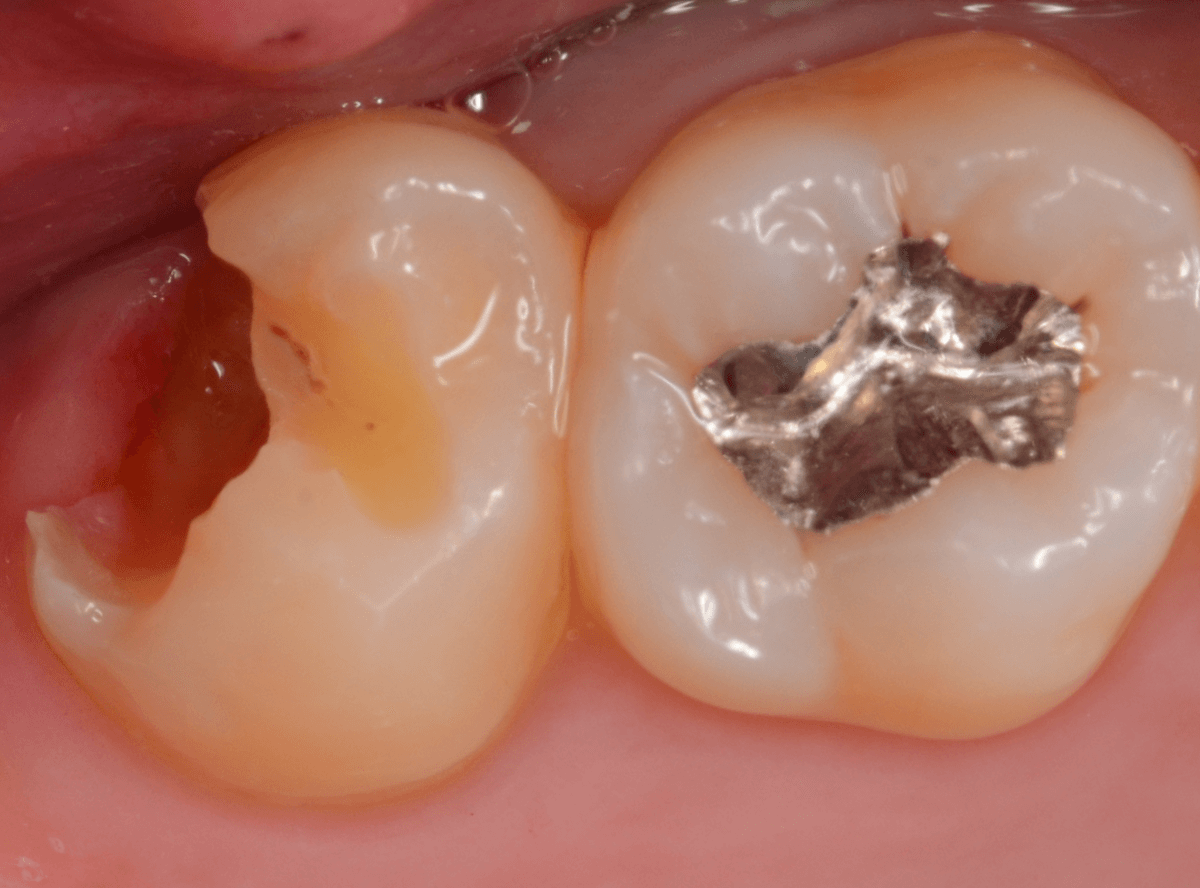

金属を外したところです。

写真では写ってしませんが、この奥に虫歯があります。

全ての虫歯を除去したところです。

抜歯した後ろのおやしらずは、元々虫歯の治療がしてありましたが、その際に抜歯しておいた方が良かったのではないかな、と思いました。